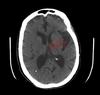

When’s the soonest you’d see any possible findings of acute ischemic stroke radiographically? - 2 ; What would you see?

3 hours; HYPERdensity representing acute thrombous/embolus in major vessels (MCA and vertebrobasilar) +/- loss of cortical gray/white differentiation